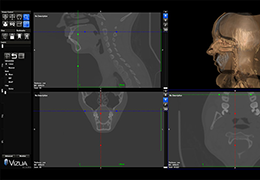

View X-Ray CT & MRI Scans Fast and Easily

Designed for surgeons, Pro Surgical 3D makes it easy to view patient scans quickly. Pro Surgical 3D facilitates the optimal 3D treatment and assessment workflows based on X-ray CT and MRI scans – and best of all, it’s FREE!

High-quality and fast 3D reconstruction and 3D rendering

Performs 3D reconstruction and volume rendering.

Multi-planar slicing.

Oblique slicing.